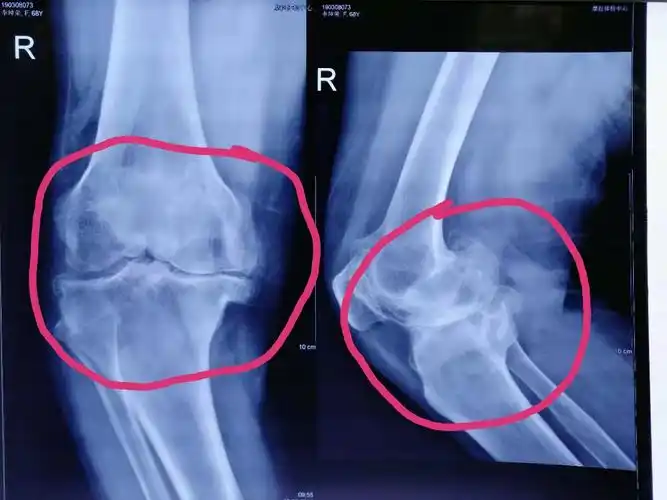

关于骨刺